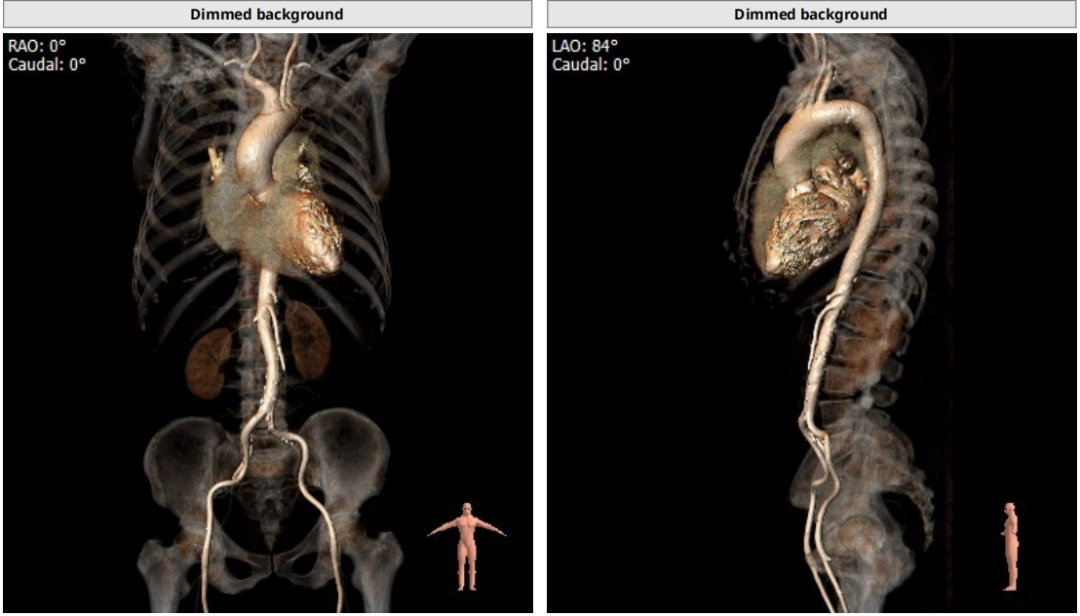

术前评估

类TYPE2型二叶瓣,极重度钙化,左冠高度稍低,右冠高度可,升主动脉增宽,最宽处约40mm,心脏角度不大,左室大,心尖部局部心肌薄弱作。

1、左冠开口低,冠脉风险偏高

2、 TYPE2型二叶瓣加上极重度钙化,影响瓣膜贴壁,瓣周漏产生机率增高。

2.冠脉风险:瓣叶较长,右冠高度尚可,左冠9.3mm偏低,但由于钙化分布广且重,瓣叶可能不会被推挤到冠脉开口,术中根据球扩进一步明确。